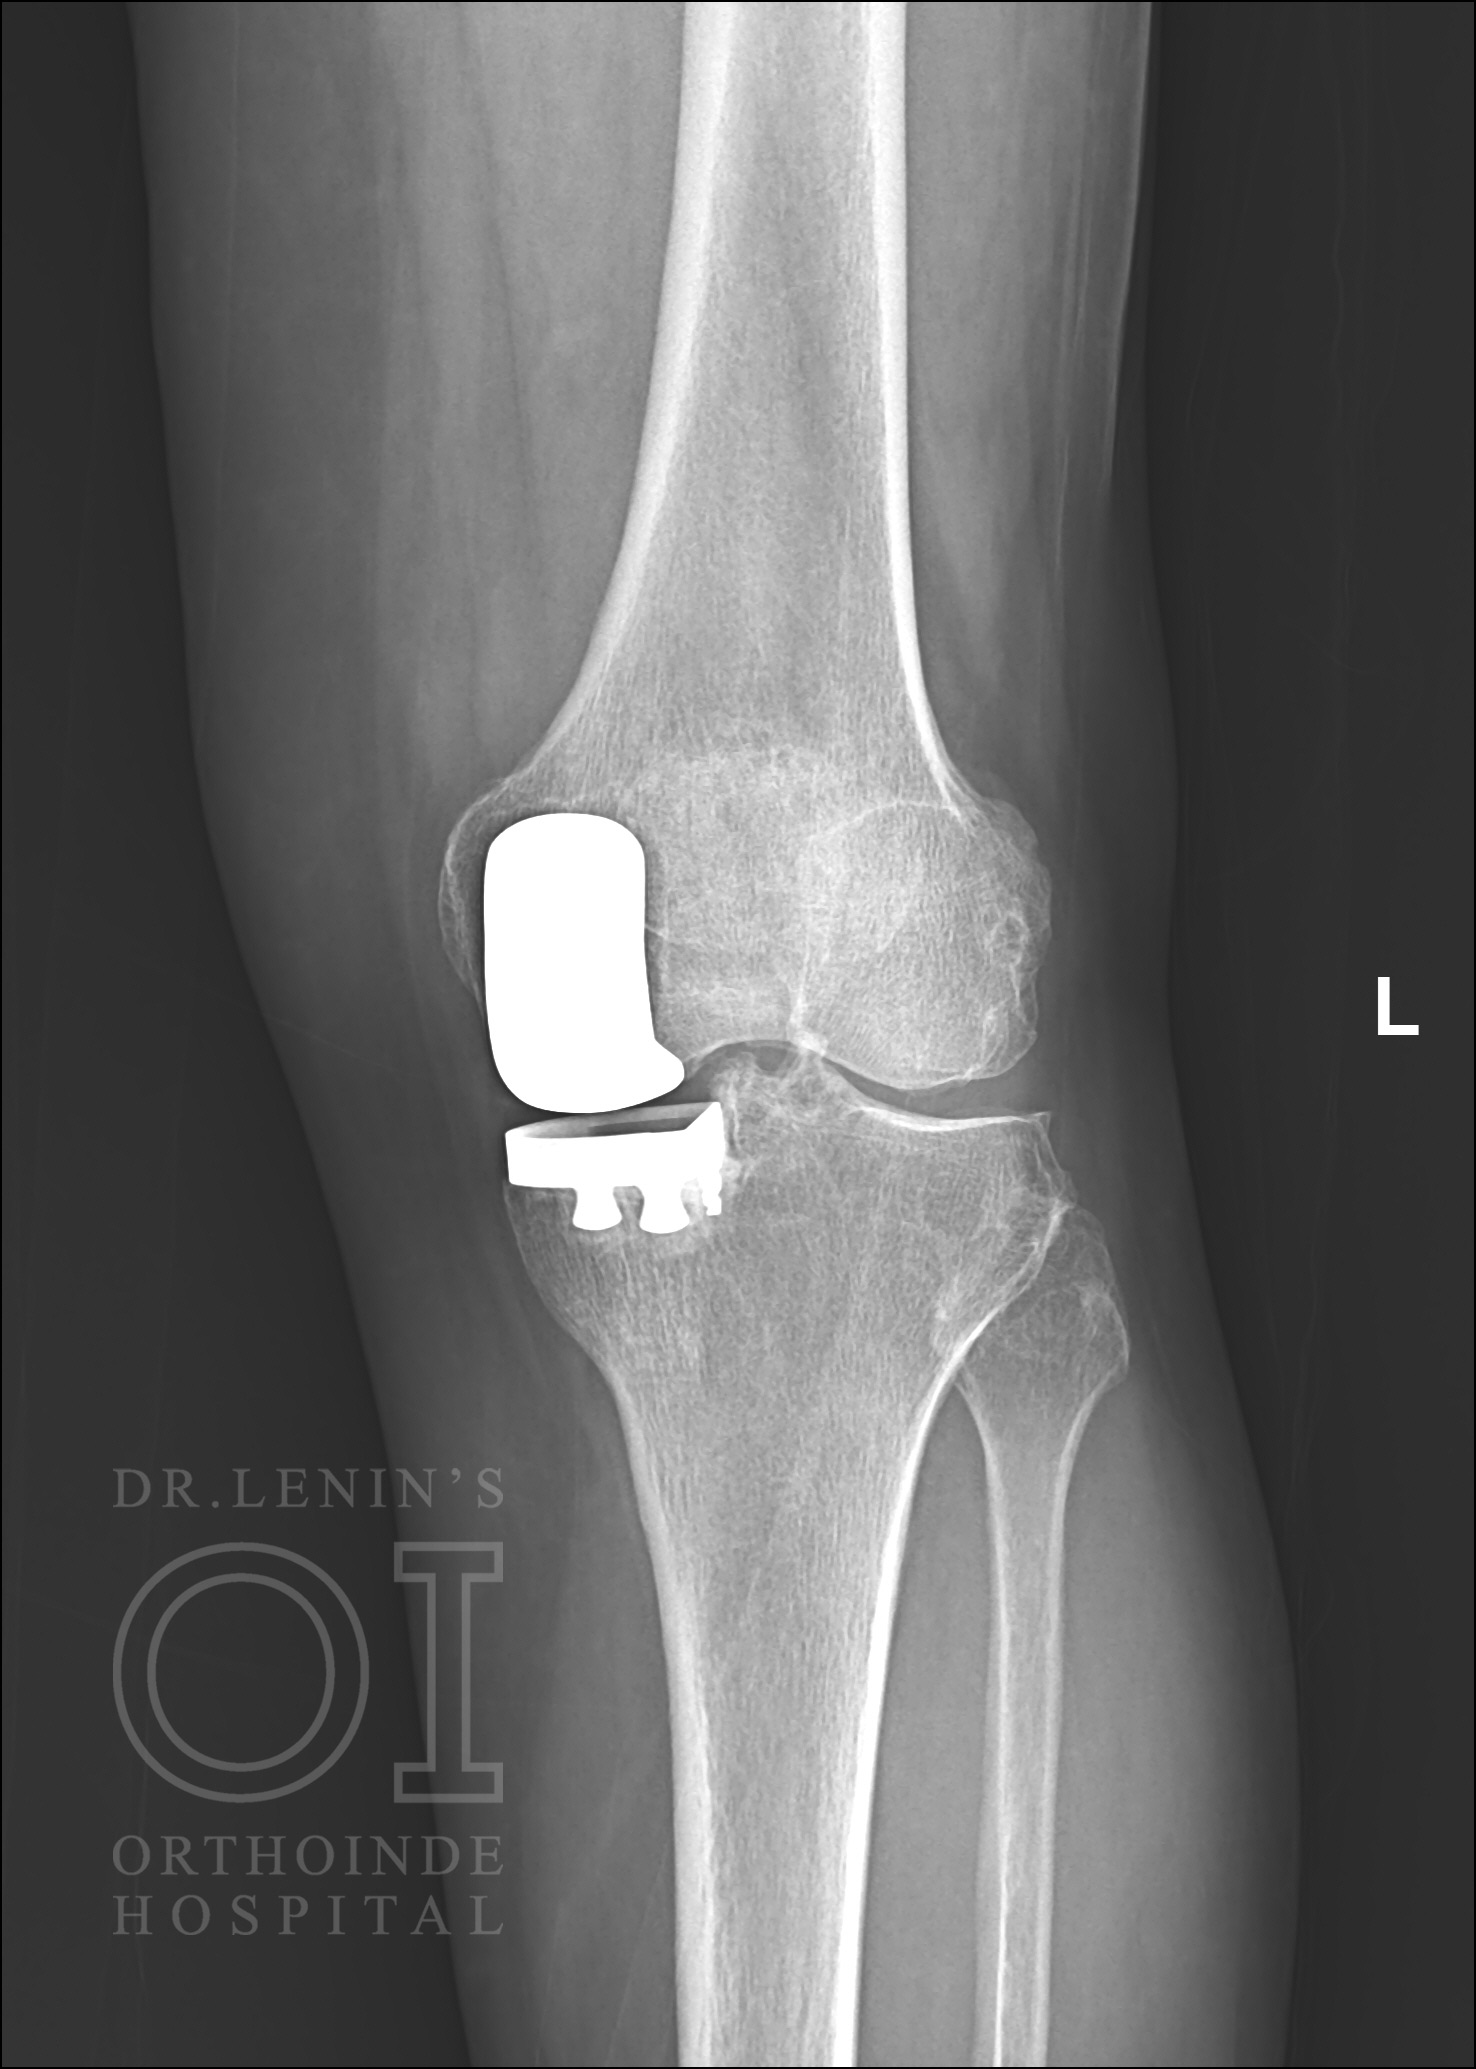

Partial (Unicompartmental) Knee replacement

If arthritis affects the only side of the knee out of the three compartments with intact ligaments, then a unicompartmental knee replacement is recommended instead of a total knee replacement. Generally, the inner compartment (medial) of the knee is more affected than the other two.

Unicompartment Knee Replacement Surgical Procedures

- The ortho surgeon makes an incision in the front part of the knee to check all the three compartments for their condition.

- Through the available x-rays and CT scans, the surgeon might have decided to go for uni-compartment knee replacement. But during the actual surgery, the surgeon will check if the two other knee compartments are healthy and the ligaments are intact.

- If the surgeon has an iota of the doubt if the unicompartment knee replacement will be unsuitable, then a total knee replacement would be performed. This contingency would be discussed with all patients who have been assessed for fitting uni-compartment knee replacement.

- If the surgeon finds the patient fit to undergo uni-compartment knee replacement, the surgeon would prepare the bone using special saws. The cartilage from the damaged knee compartment would be removed and the bone would be shaped to take in the impact

- The metal covering of the unicompartment knee replacement is then placed to the bones (both the thigh bone and the shin bone) and cemented firmly.

- Then the surgeon proceeds to place a plastic insert between the two metal implants to create a smooth moving surface.

- The muscles are then stitched together and a drain is placed which assists in healing. The wound is then drapped in dressings and the patient is moved out of the surgical theatre.